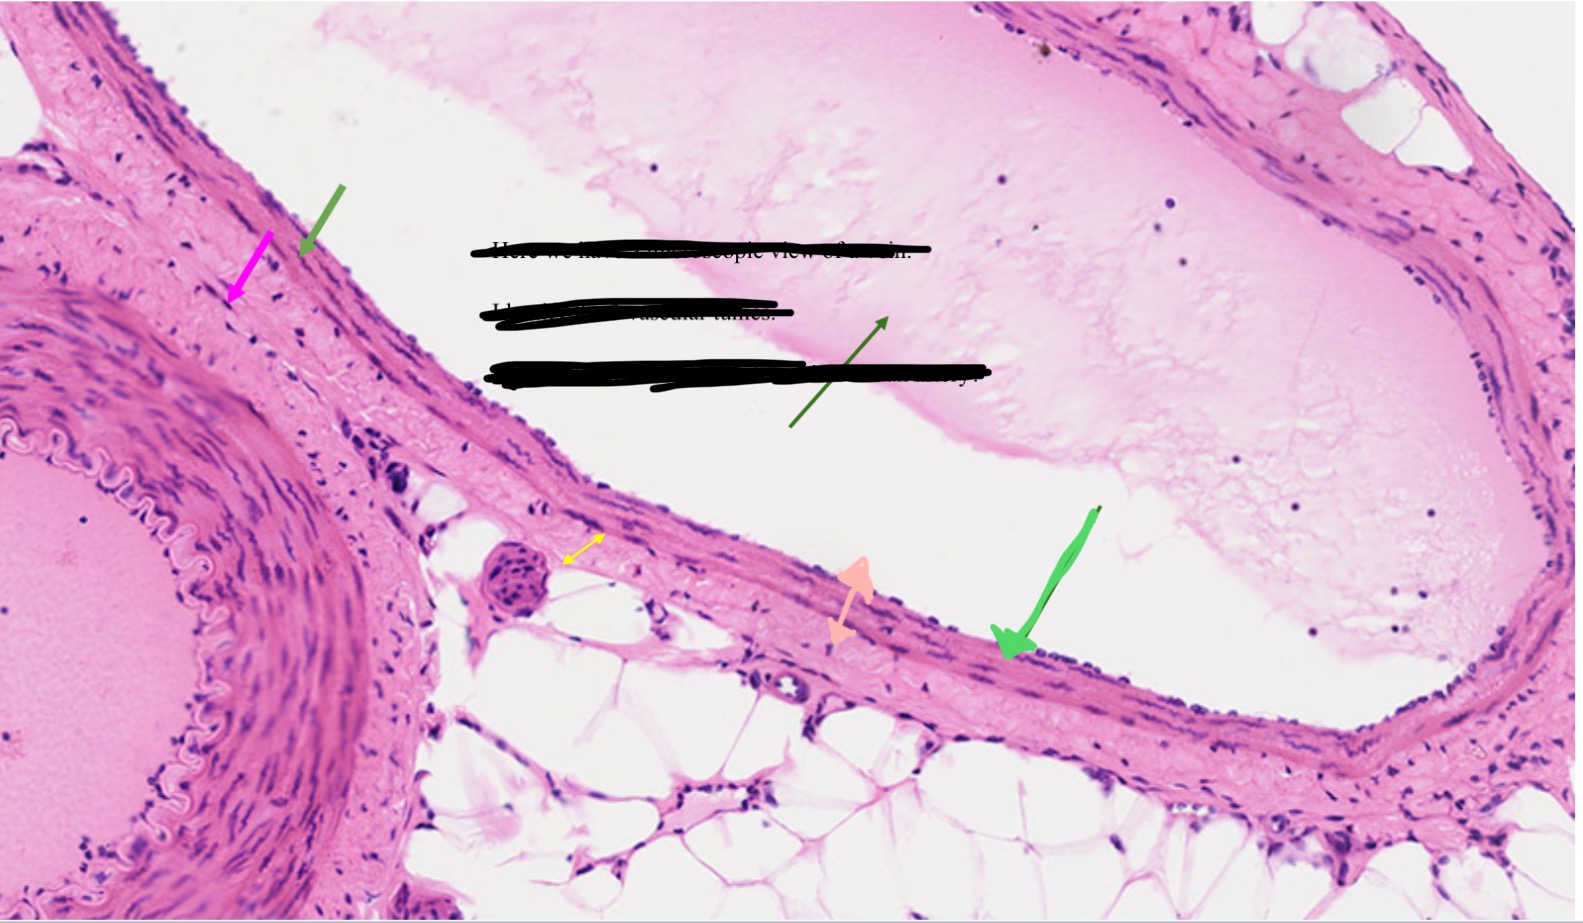

Tunica intima

Name the blue arrow

Lines lumen and release vasoactive chemicals

Function of tunica intima

Venous valves

Name the pink arrow

Prevent backflow of blood

Function of venous valves

Tunica media

Name green arrow

Vasoconstriction and vasodilation

Function of tunica media

Tunica externa

Name the purple arrow

Anchor and bind vessel

Function of tunica externa

Artery

Artery or vein?

Vein

Artery or vein?